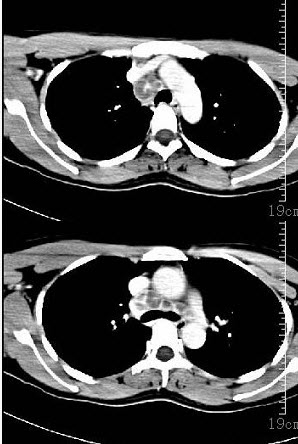

- 单项选择题女性35岁,发热、盗汗近3个月,颈部摸到多个结节,CT扫描如图所示,请选择最可能的诊断()。

- D